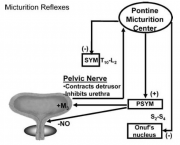

| 06:16, 3 באוגוסט 2014 | נוירוגנית3.png (קובץ) |  |

114 קילו־בייטים | Motyk | 1 | |